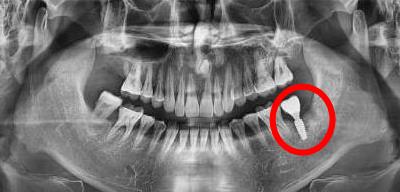

種植體(ti) 周圍炎,嚴(yan) 重影響種植體(ti) 的穩定性和長期性

通常來說,種植牙定期複診主要是拍片,檢查種植牙周圍骨頭的穩定情況,如果口腔清潔不好,口內(nei) 牙菌斑和牙結石較多,需要及時洗牙去除;檢查種植牙各個(ge) 連接部分是否出現鬆動、牙齒咬合是否正常,以及可以監督**認真護理口腔,養(yang) 成良好習(xi) 慣(戒煙)等,如果一旦發現問題,就需要醫生及時處理。

後牙種植牙拍片